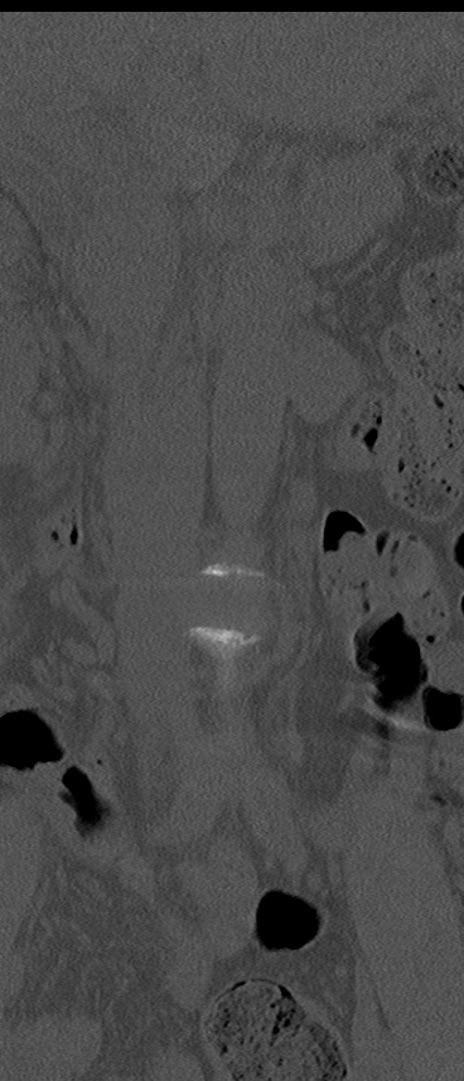

【整形】TIPS症例4 腰椎CT(冠状断像)

腰椎CT